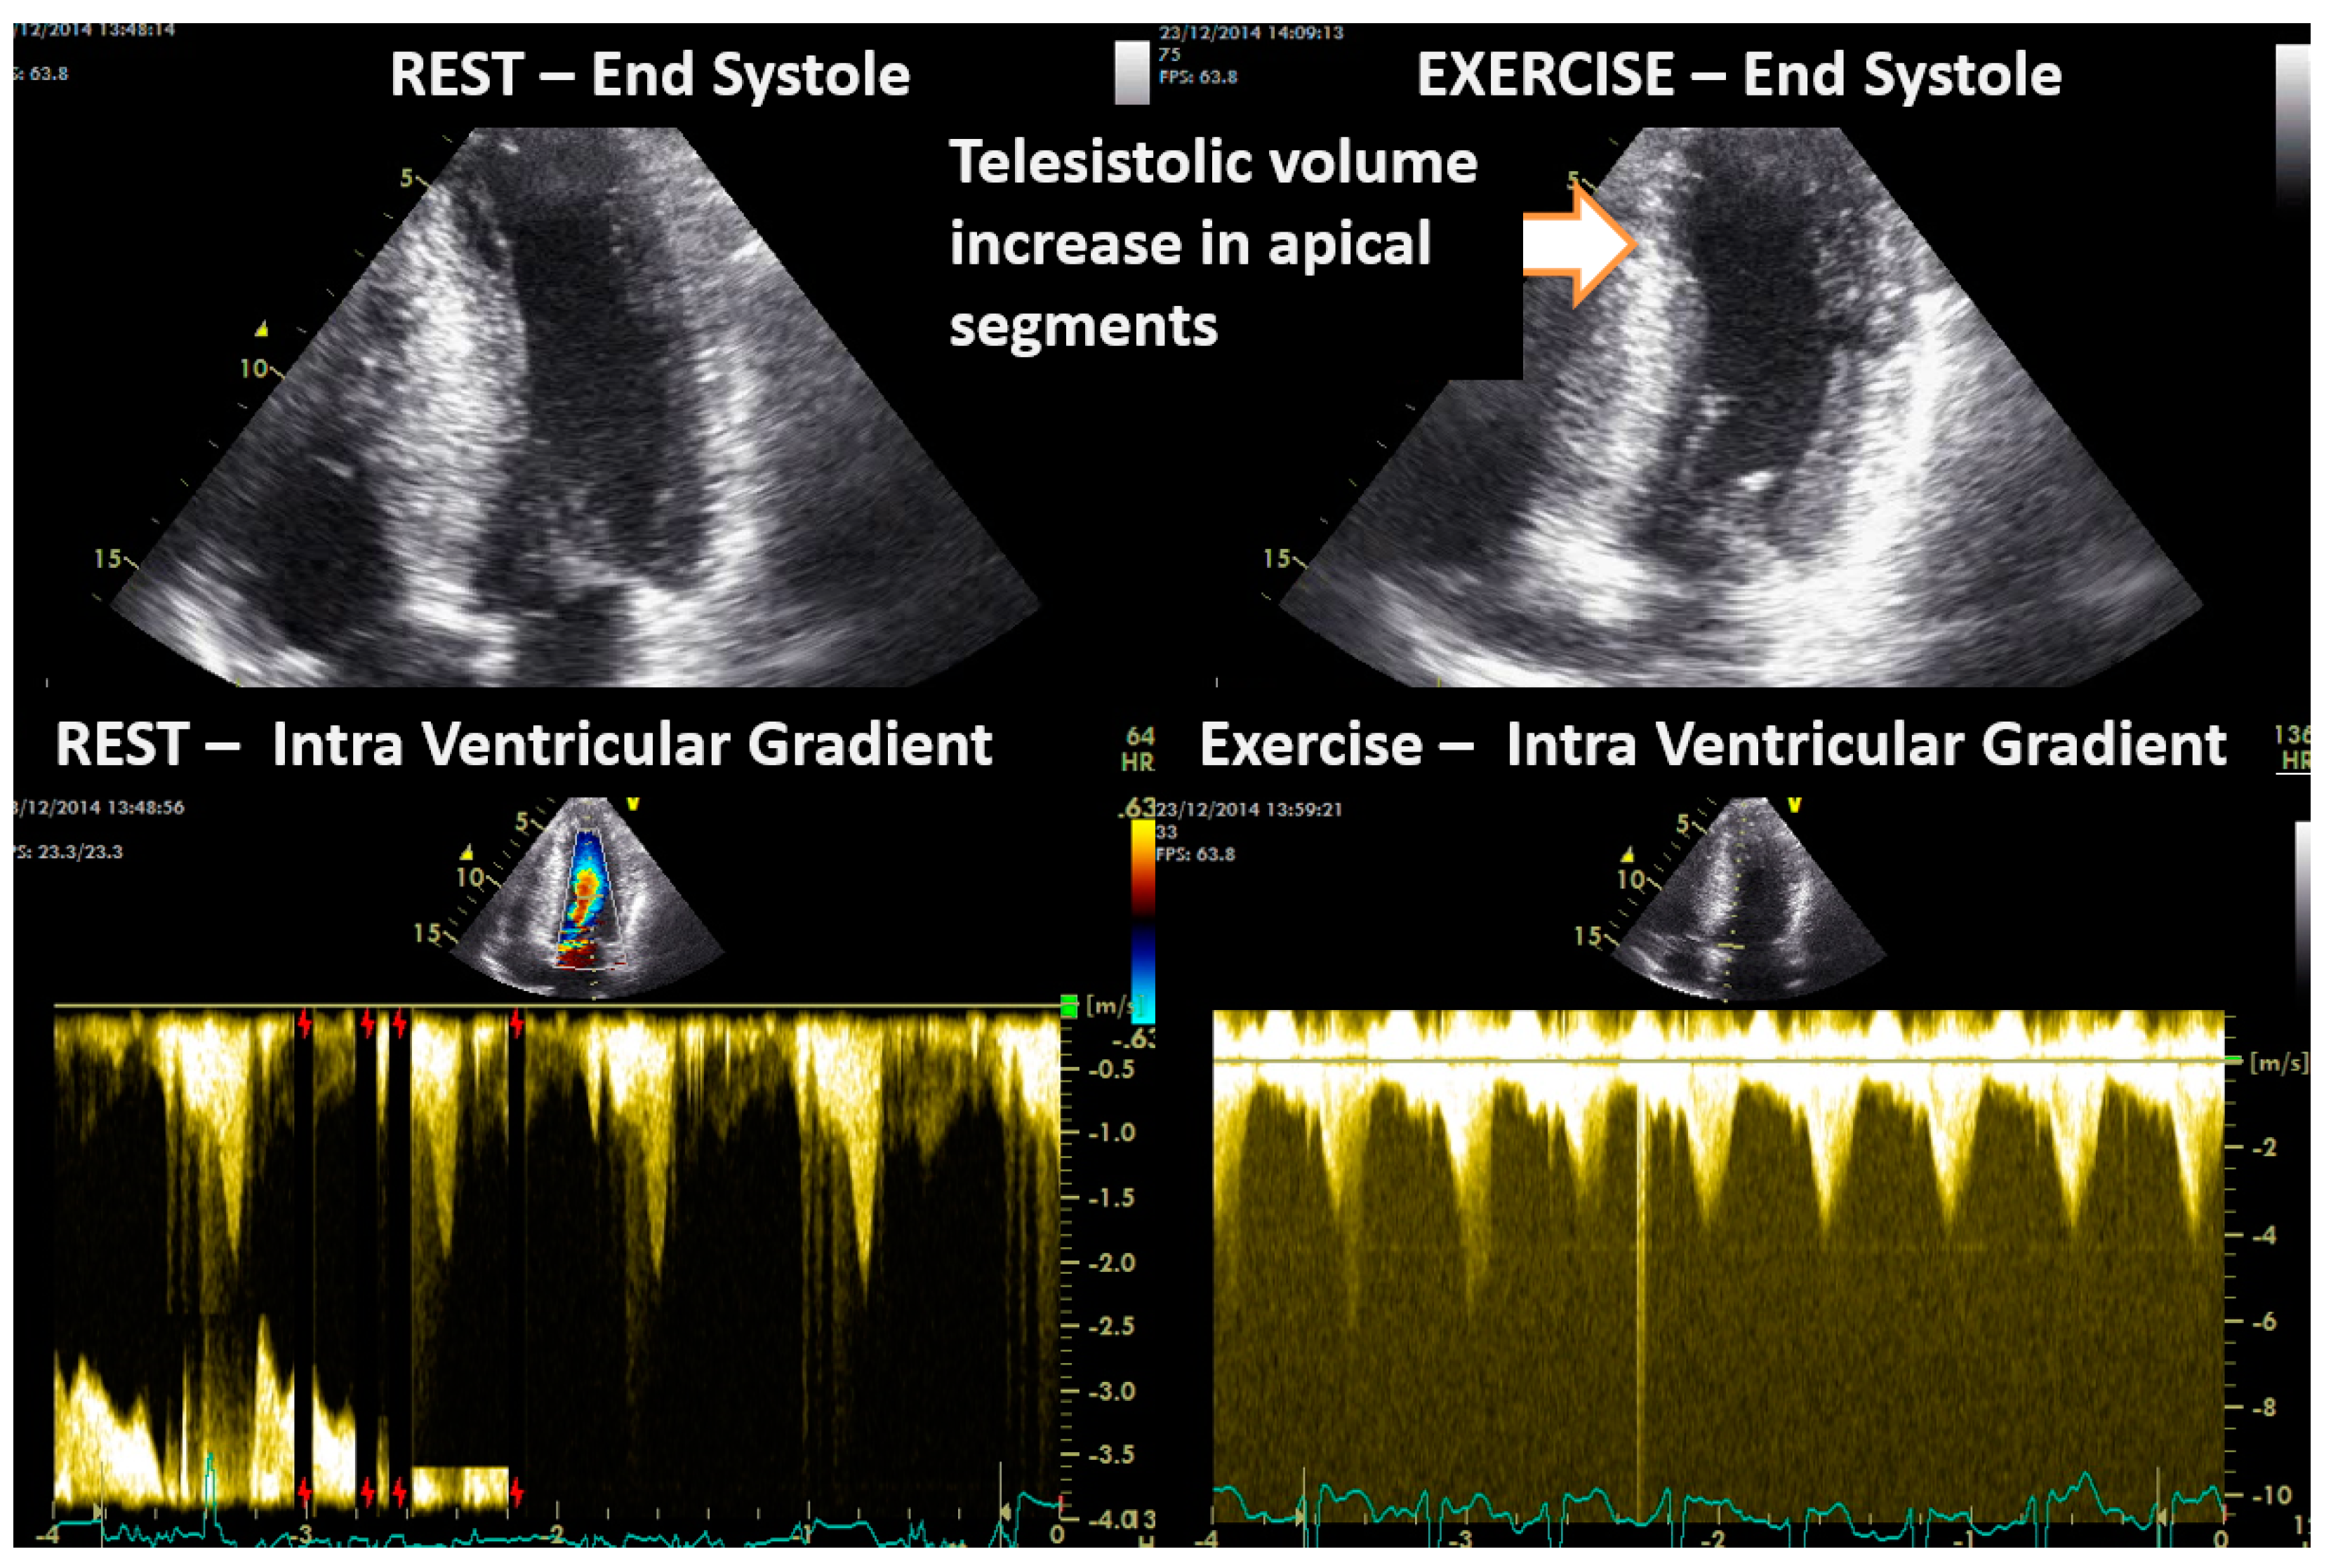

- Cotrim, C.; Palinkas, E.D.; Cotrim, N. The Importance of Left Ventricular Outflow Tract and Mid-Ventricular Gradients in Stress Echocardiography: A Narrative Review. J. Clin. Med. 2023, 12, 5292. [Google Scholar] [CrossRef] [PubMed]

- Lopes, L.R.; Cotrim, C.; Cruz, I.; Picano, E.; Pinto, F.; Pereira, H. Left ventricular outflow tract obstruction as a primary phenotypic expression of hypertrophic cardiomyopathy in mutation carriers without hypertrophy. Int. J. Cardiol. 2014, 176, 1264–1267. [Google Scholar] [CrossRef] [PubMed]

- Cotrim, C.; Lopes, L.R.; Almeida, A.R.; Miranda, R.; Ana, A.G.; Cotrim, H.; Andrade, J.P.; Picano, E.; Carrageta, M. Efficacy of beta-blocker therapy in symptomatic athletes with exercise-induced intra-ventricular gradients. Cardiovasc. Ultrasound. 2010, 8, 38. [Google Scholar] [CrossRef] [PubMed]

- Cabrera Bueno, F.; Rodríguez Bailón, I.; López Salguero, R.; Doblas, J.J.G.; Cabeza, A.P.; Hernández, J.P.; Franco, A.D.; Hidalgo, L.M.; de Teresa Galván, E. Obstrucción dinámica intraventricular izquierda inducida por esfuerzo [Dynamic left ventricular outflow tract obstruction induced by exercise]. Rev. Esp. Cardiol. 2004, 57, 1179–1187. [Google Scholar] [CrossRef] [PubMed]

- Zywica, K.; Jenni, R.; Pellikka, P.A.; Faeh-Gunz, A.; Seifert, B.; Attenhofer Jost, C.H. Dynamic left ventricular outflow tract obstruction evoked by exercise echocardiography: Prevalence and predictive factors in a prospective study. Eur. J. Echocardiogr. 2008, 9, 665–671. [Google Scholar] [CrossRef]

- Saeed, S.; Vegsundvåg, J. Usefulness of Stress Echocardiography in Assessment of Dynamic Left Ventricular Obstructions: Case Series and Review of the Literature. Cardiology 2021, 146, 441–450. [Google Scholar] [CrossRef]

- Alhaj, E.K.; Kim, B.; Cantales, D.; Uretsky, S.; Chaudhry, F.A.; Sherrid, M.V. Symptomatic exercise-induced left ventricular outflow tract obstruction without left ventricular hypertrophy. J. Am. Soc. Echocardiogr. 2013, 26, 556–565. [Google Scholar] [CrossRef] [PubMed]

- Dores, H.; Mendes, L.; Ferreira, A.; Santos, J.F. Symptomatic Exercise-induced Intraventricular Gradient in Competitive Athlete. Arq. Bras. Cardiol. 2017, 109, 87–89. [Google Scholar] [CrossRef] [PubMed]